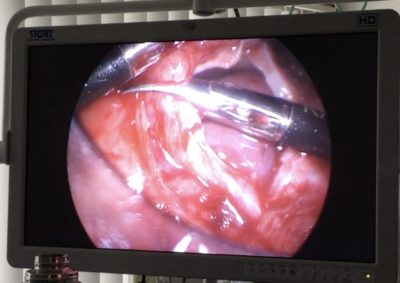

軟部組織外科 注意 ボタンをクリックした先に、治療中および手術中の画像が説明で使用されている場合がございます。 そのような画像に弱い方は閲覧なさらないようお願いいたします。 軟部組織外科 異物による唾液腺の穿孔 軟部組織外科 犬の尿管結石に対する結石摘除 救急・集中治療軟部組織外科 猫の尿管結石に対する尿管切除吻合術#11 軟部組織外科 PSS 犬の門脈体循環シャント 軟部組織外科 猫のPSS 軟部組織外科救急・集中治療 胆嚢摘出 軟部組織外科 予防的胃固定術 Lap−Gastropexy 軟部組織外科 特発性出血性心タンポナーゼ 軟部組織外科 猫の腎膿瘍 軟部組織外科 犬の特発性乳び胸 軟部組織外科 短頭種気道症候群 軟部組織外科 犬の腟脱 <«789101112131415> 症例カテゴリー 放射線治療整形外科軟部組織外科脳神経外科内科腫瘍外科救急・集中治療リハビリテーション科腫瘍内科内視鏡科脳神経科呼吸器外科中医・漢方猫の腎移植循環器科